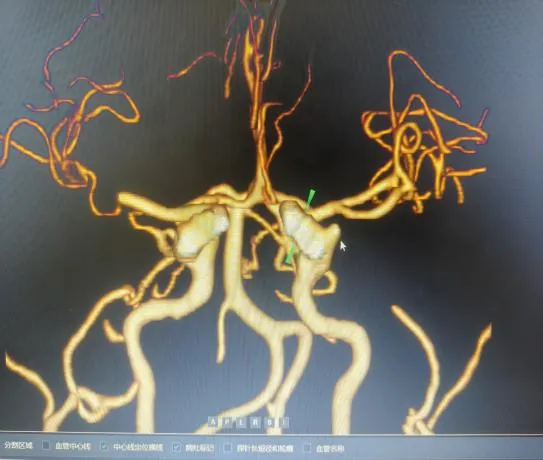

“时间就是大脑,每延迟一分钟,就有190万个神经细胞不可逆坏死!”面对紧急病情,医护团队争分夺秒。快速完成头颅CT等检查后,明确患者符合静脉溶栓指征且无绝对禁忌证,与家属协商签署溶栓同意书后,于22:04立即对患者进行阿替普酶溶栓治疗,DNT时间仅34分钟。然而,溶栓后复查影像学显示,患者大脑中动脉主干仍大血管闭塞,单纯溶栓未彻底开通血管,病情高危。关键时刻,救治团队当机立断,决定采用当前急性大血管闭塞性脑卒中的前沿救治方案——“溶栓桥接取栓”,为患者打通生命通道。

手术室内,神经内科张奕主任凭借丰富经验和精湛技术,在数字减影血管造影机引导下,经毫米级微创通道,将取栓器械精准送达闭塞血管核心部位。经不到1小时操作,成功完整取出堵塞血管的栓子,闭塞血管再通,脑部血供恢复。术后复查头颅 CT显示低灌注区脑组织全部存活。